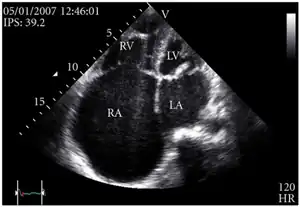

Definitive diagnosis is made by echocardiogram, which is capable of measuring both the presence and the severity of the TR, as well as right ventricular dimensions and systolic pressures.[12]

Transthoracic echo: enlargement of the right atrium in TR and mitral valve disease -